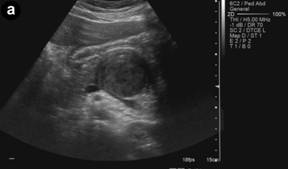

A 13-year-old boy referring postprandial fullness and nausea for the past three months. Weight loss and pain in the upper quadrants of the abdomen recently occurred. Blood workup, including tumor markers, was unremarkable. Abdominal ultrasound (Figure 1) showed a well-circumscribed heterogeneous hypoechoic mass in the region of the pancreatic body/tail. Unenhanced CT (Figure 2) confirmed the pancreatic lesion with a slightly heterogeneous density. No calcifications were identified. T2-weighted MR images (Figure 3ab) showed a 4.8 cm heterogeneously hyperintense lesion in the pancreas, showing a hypointense rim. This rim was also hypointense on T1-weighted images (Figure 3c), consistent with the presence of a tumoral fibrous pseudocapsule. T1-weighted images also showed some internal areas of increased signal intensity compatible with hemorrhage.

Figure 1. a. Transverse upper abdominal ultrasonography: hypoechoic heterogeneous mass of the pancreas. b. Doppler ultrasonography showing no apparent tumoral vascularization. |

On ultrasound, solid pseudopapillary tumor presents as a well-circumscribed heterogeneous mass surrounded by a pseudocapsule of compressed pancreatic tissues and reactive fibrosis, sometimes with central cystic areas of necrosis [6]. The capsule may be visualized as an echogenic or, less commonly, hypoechoic rim at ultrasound and typically hypoattenuating at CT [4]. Unenhanced CT may identify hemorrhage and tiny calcifications [6, 7].